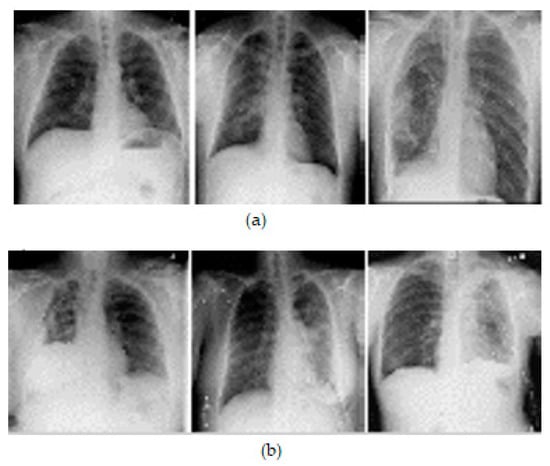

3.2. Data Preprocessing

3.3. Data Augmentation